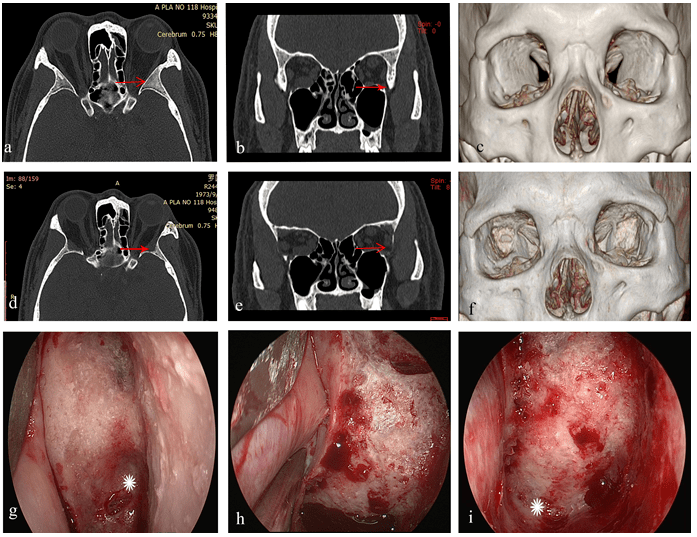

内镜下经结膜径路经眶眶外侧壁深部减压术_手术_临床_切口